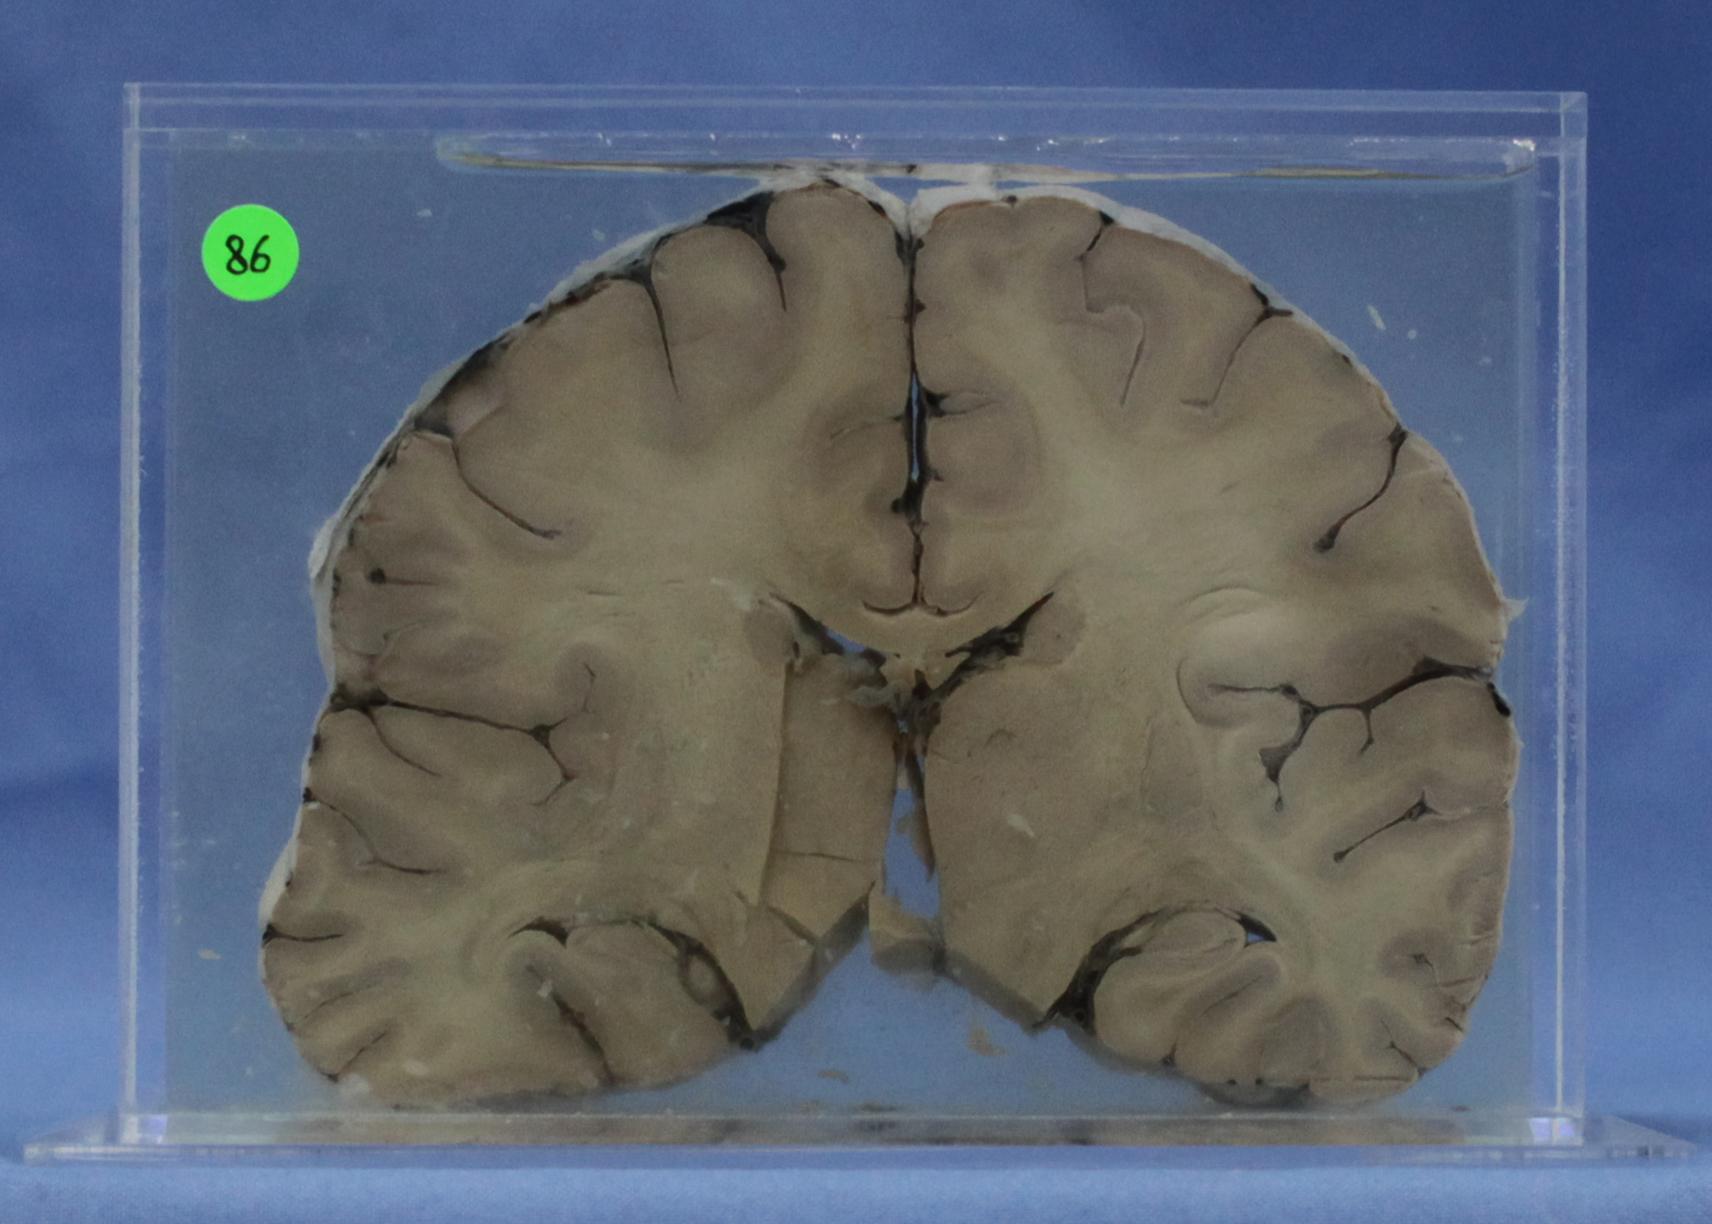

寄生虫病113-86. 脑疟疾

脑水肿,脑回变宽变扁,蛛网膜充血。脑切面白质中见多个针尖大小的软化灶。